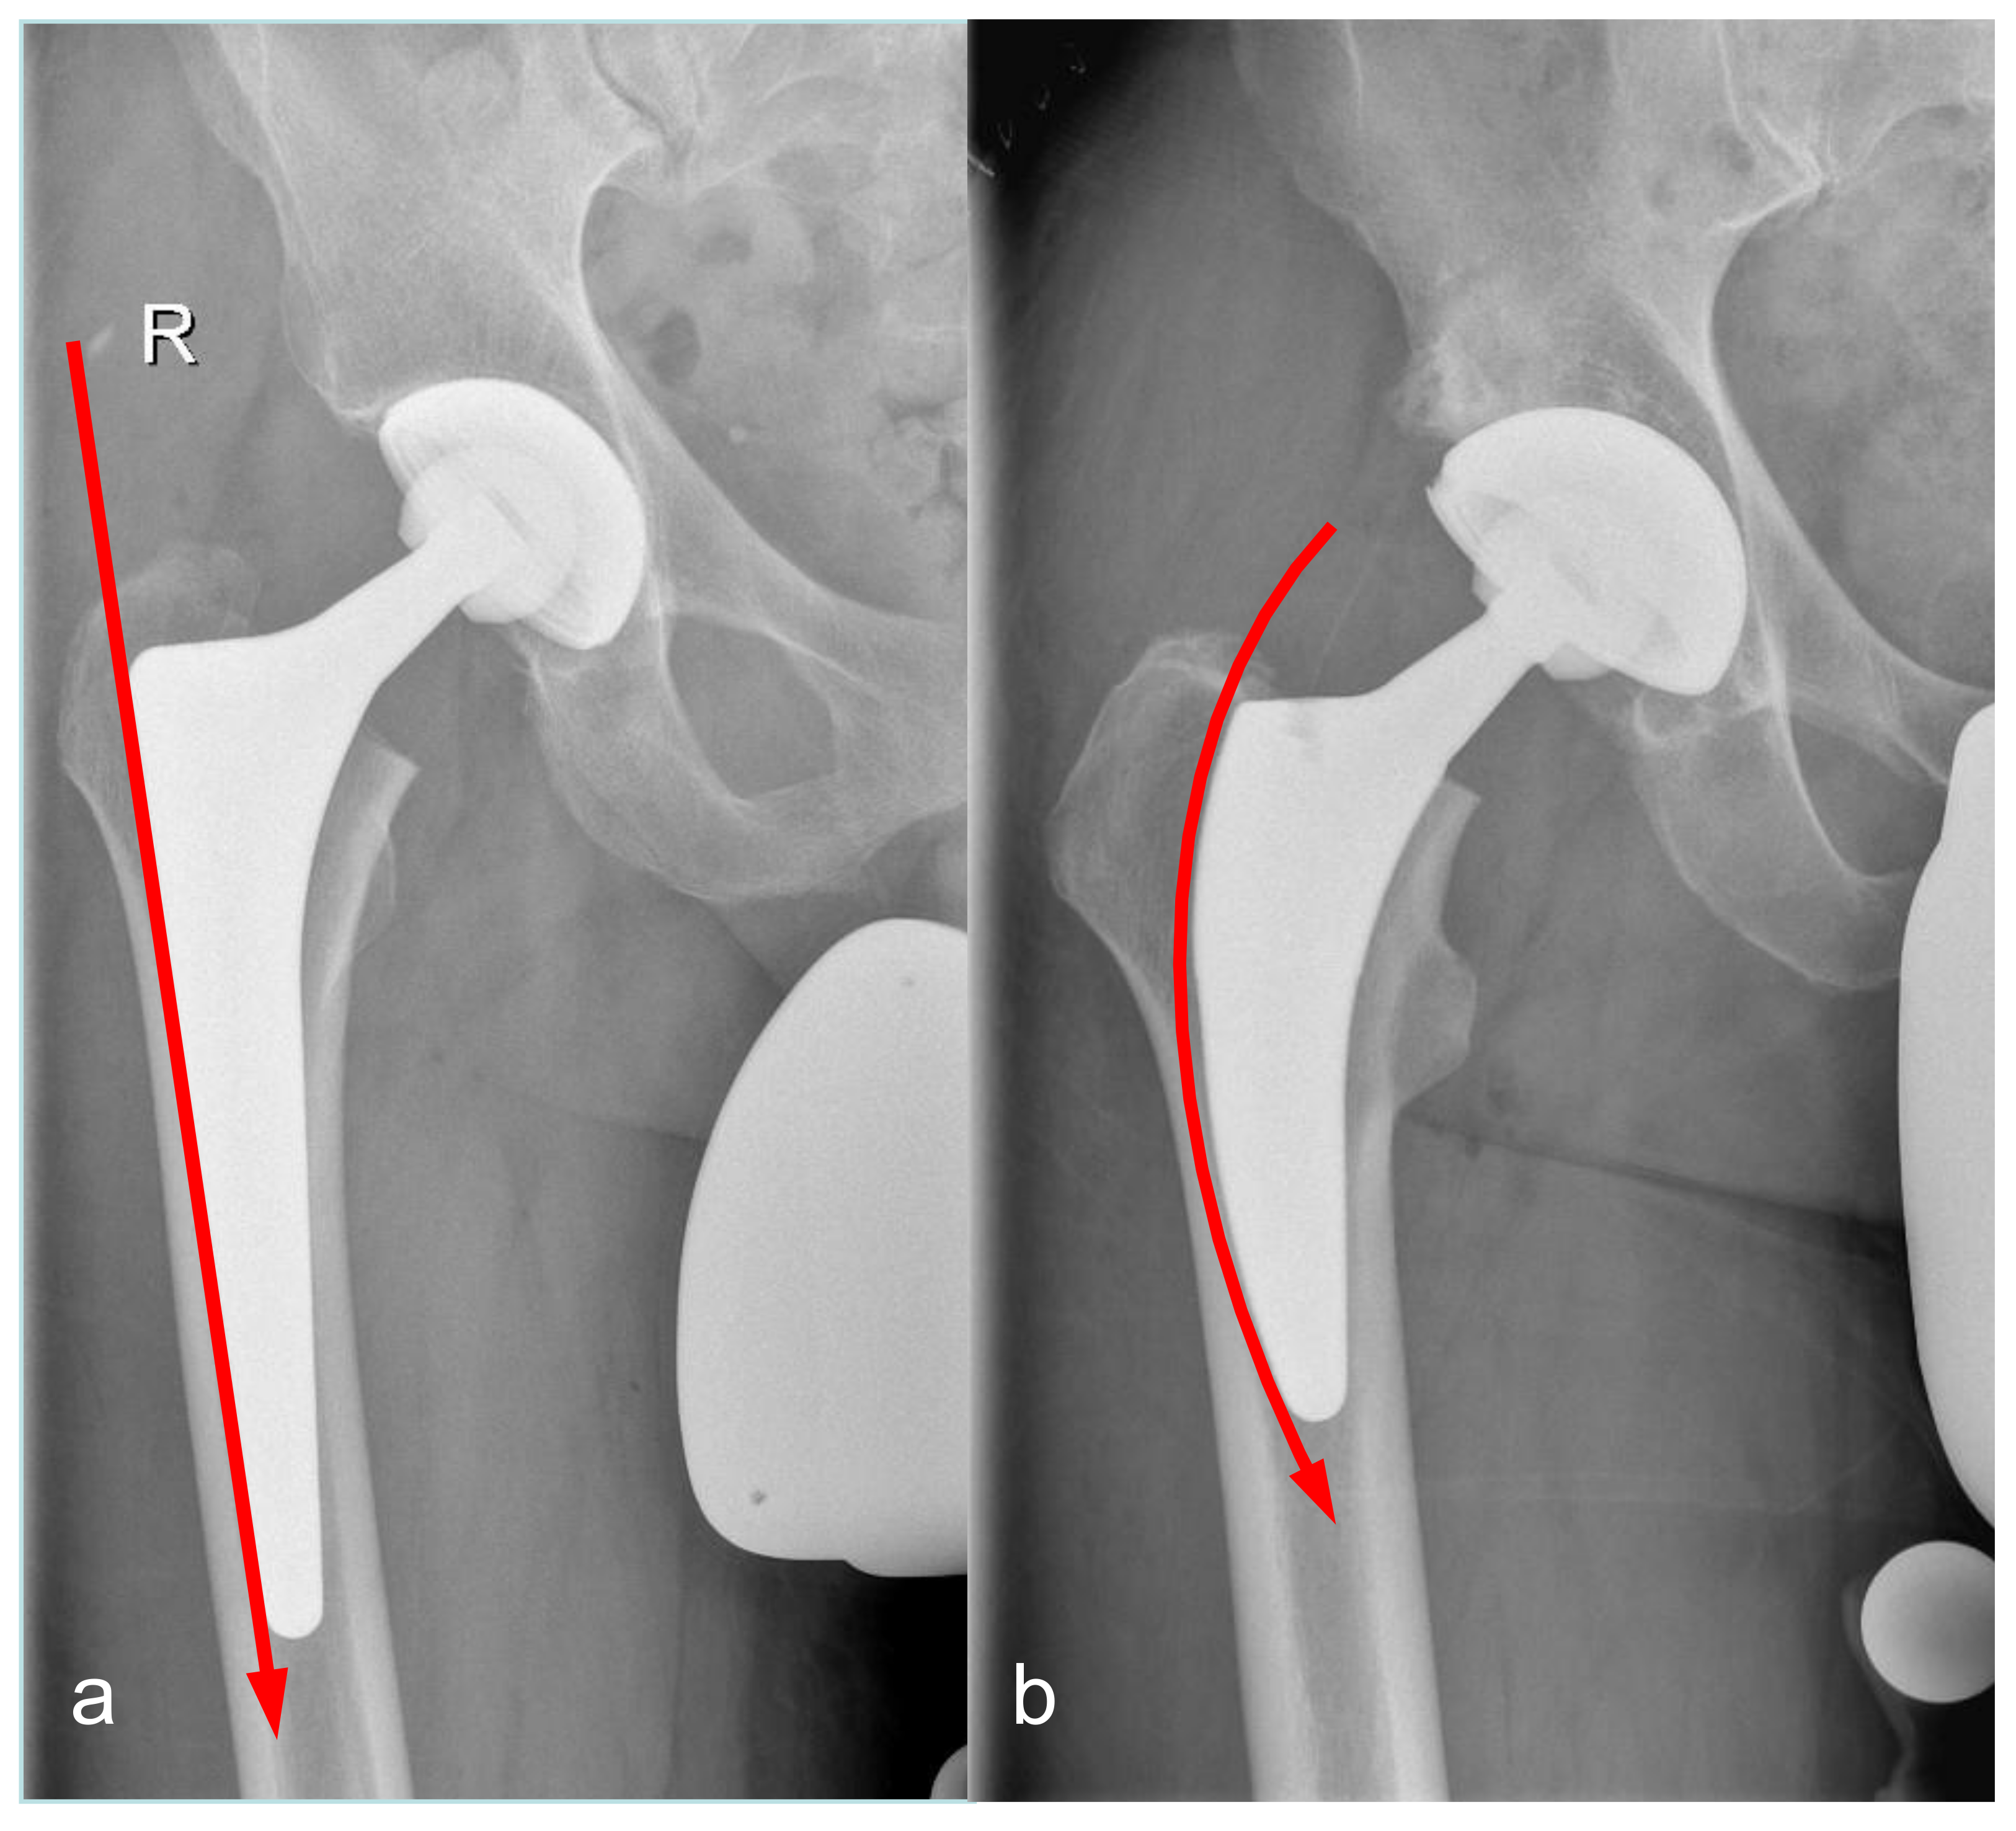

2.3. Surgeries and Implant Characteristics